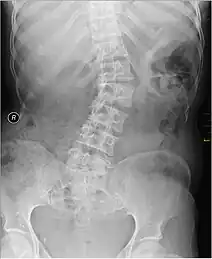

| Kyphosis (left) and scoliosis (right) depicting iliocostal contact (a) | |

Though radiological imaging is not needed for iliocostal friction syndrome diagnosis, it is often uses to assess for underlying conditions and rule out differential diagnosis. Imaging such as the use of an x-ray can reveal irregularities of the surfaces of the lower ribs and iliac crest or abnormally long 12th ribs, which may give suspicion to the diagnosis of iliocostal friction syndrome.[3][6] Computed tomography (CT) scans can reveal kyphotic deformities, including a reduced distance between the lower ribs and the iliac crest, giving rise to the possibility of iliocostal contact.[19]